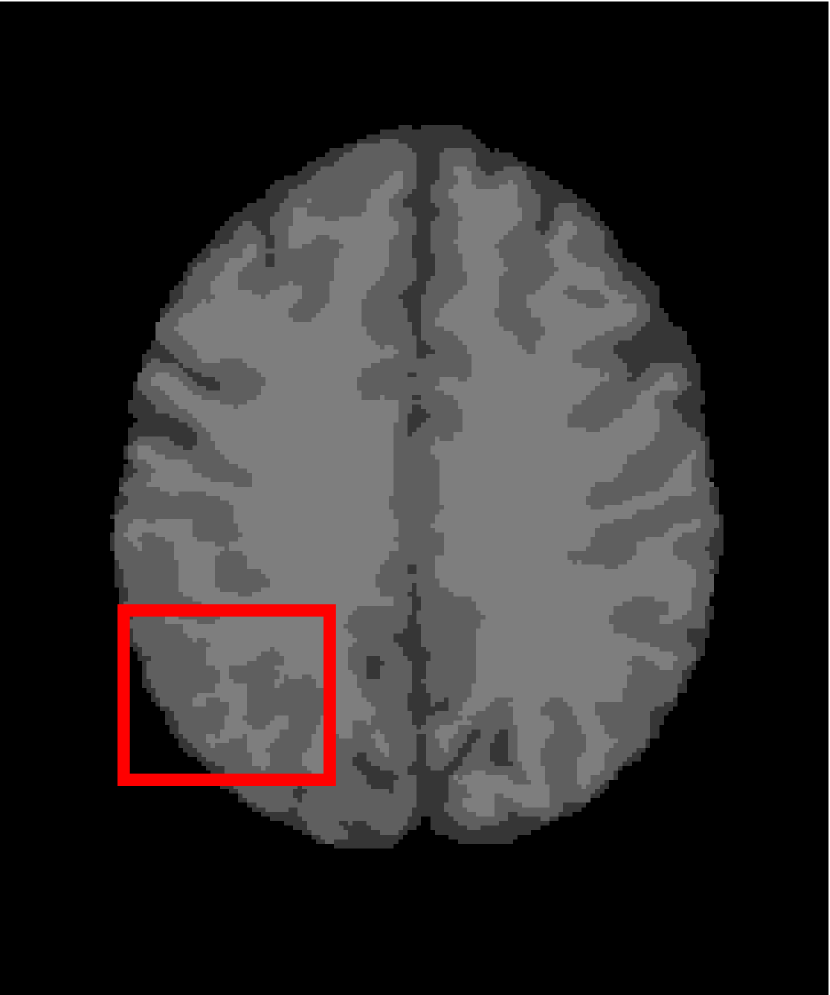

4.4.2 Results on Medical Images

Next, we representatively segment five medical images from BrianWeb. They are represented as five slices in the axial plane with a sequence of 70, 80, 90, 100 and 110, which are generated by T1 modality with slice thickness of 1mm resolution, 9% noise and 20% intensity non-uniformity. Here, we set c=4𝑐4c=4 for all cases. The comparison between WRFCM and its peers are shown in Fig. 9 and Table II. The best values are in bold.

Figure 9: Segmentation results on five medical images. The parameter: ϕ=5.35italic-ϕ5.35\phi=5.35. From top to bottom: noisy images, ground truth, and results of FCM_S1, FCM_S2, FLICM, KWFLICM, FRFCM, WFCM, DSFCM_N, and WRFCM.

By a view of the marked red square in Fig. 9, we find that FCM_S1, FCM_S2, FLICM, KWFLICM and DSFCM_N are vulnerable to noise and intensity non-uniformity. They give rise to the change of topological shapes to some extent. Unlike them, FRFCM and WFCM achieve sufficient noise removal. However, they produce overly smooth contours. Compared with its seven peers, WRFCM can not only suppress noise adequately but also acquire accurate contours. Moreover, it yields the visual result closer to ground truth than its peers. As Table II shows, WRFCM obtains optimal SA, SDS and MCC results for all five medical images. As a conclusion, it outperforms its peers visually and quantitatively.